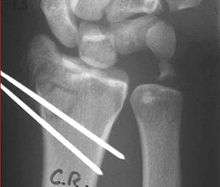

Reduction

Closed management of a distal radius fracture involves first anesthetizing the affected area with a hematoma block, regional anesthesia, sedation or a general anesthetic.

Manipulation generally includes first placing the arm under traction and unlocking the fragments. The deformity is then reduced with appropriate closed manipulations (depending on the type of deformity) reduction, after which a splint or cast is placed and an X-ray is taken to ensure that the reduction was successful. The cast is usually maintained for about 6 weeks.

Closed treatment is frequently unsuccessful in maintaining a good position in adults, because there is frequently comminution of the fracture. Re-displacement and deformity can reoccur with an unacceptable ultimate result.